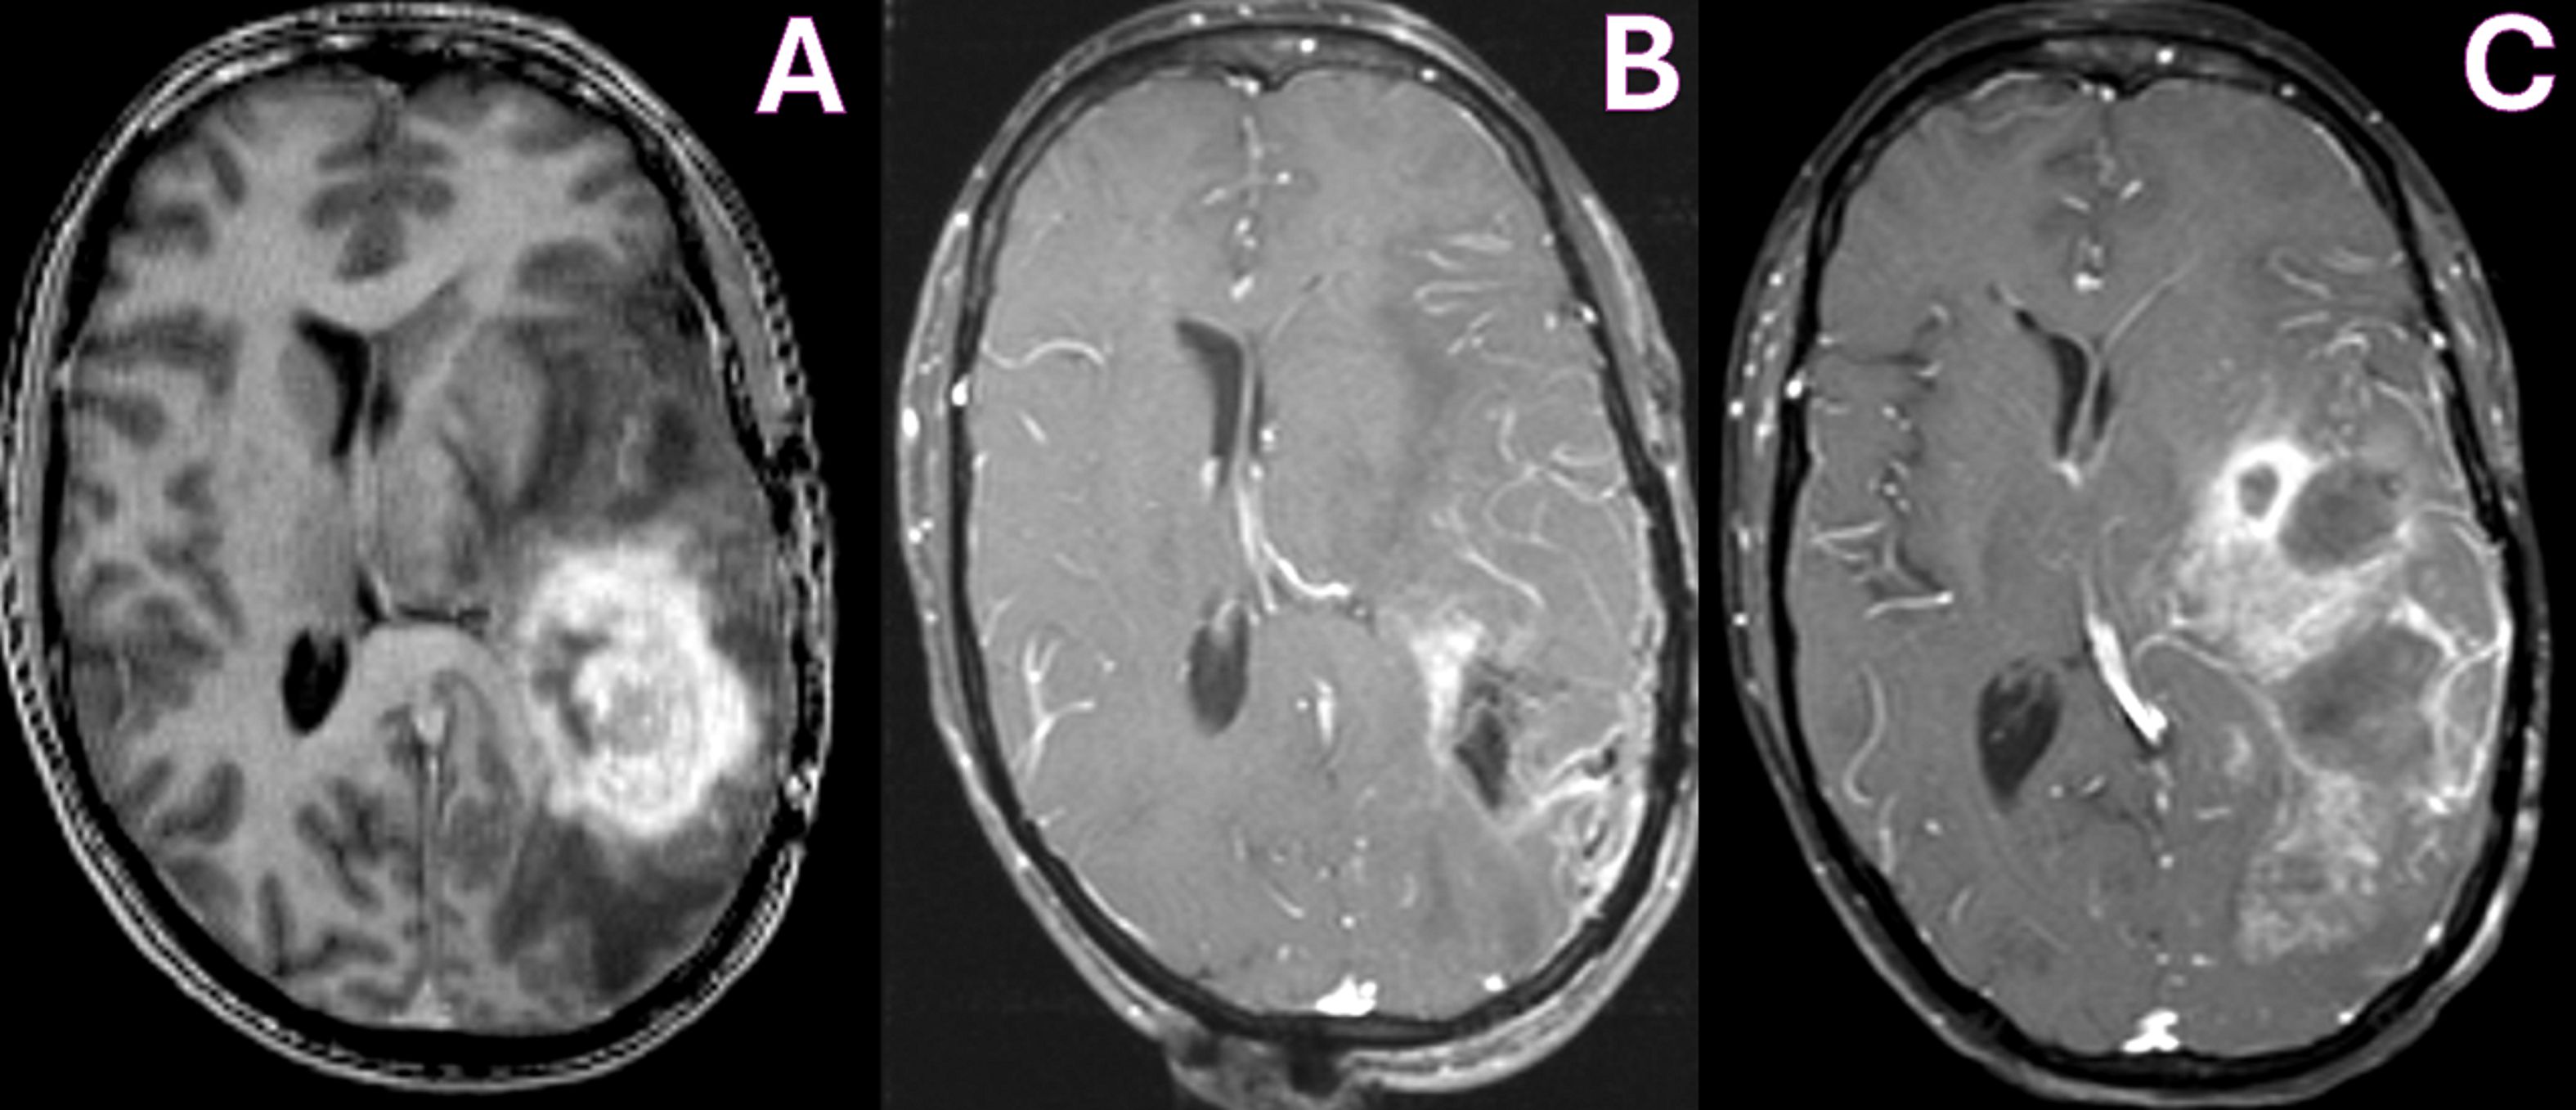

In March 2011, she presented to our clinic presenting with language dysfunction, right-sided weakness (hemiparesis), and seizures. Her MRI revealed a large enhancing mass in the left temporoparietal lobe with significant vasogenic edema consistent with progressive disease (Figure 1A).

Figure 1. MRI T1-WI with contrast showing pre-operative tumor enhancement in the left temporoparietal lobe (A), with improvement in enhancing tumor on immediate post-operative day 1 (B) and increased enhancement due to tumor recurrence at 4 months (C).

She underwent surgery under general anesthesia. Anesthetics propofol and remifentanil were used for their favorable pharmacokinetic and physiologic profile in the gravid patient. Propofol was selected for its rapid induction and emergence, as well as its ability to reduce cerebral metabolic rate, cerebral blood flow, and intracranial pressure. Although remifentanil freely crosses the placenta, it was selected because of its short half-life and predictable metabolism, which would minimize fetal exposure. Intraoperative monitoring of fetal heart rate and uterine contractions was performed by an obstetric nurse with fetal ultrasound and cardiography. She underwent a successful left temporoparietal craniotomy and tumor resection, with implantation of six Gliadel wafers in the surgical bed (Figure 1B). Histopathology confirmed the diagnosis of a grade IV astrocytoma, IDH-1 mutant, ATRX loss, and MGMT unmethylated.

In July 2011, 4 months after surgery and 2 months after initiation of Avastin therapy, she presented with worsening aphasia and weakness and had breakdown of her cranial wound. Her MRI revealed increased enhancement, acute hemorrhages in the frontal and temporal lobes, and obstructive hydrocephalus (Figure 1C). Given the poor prognosis, the patient was transitioned to hospice care. The baby girl remains healthy and is achieving developmental milestones beyond 14 years. Clinical time is outlined in Table 1.